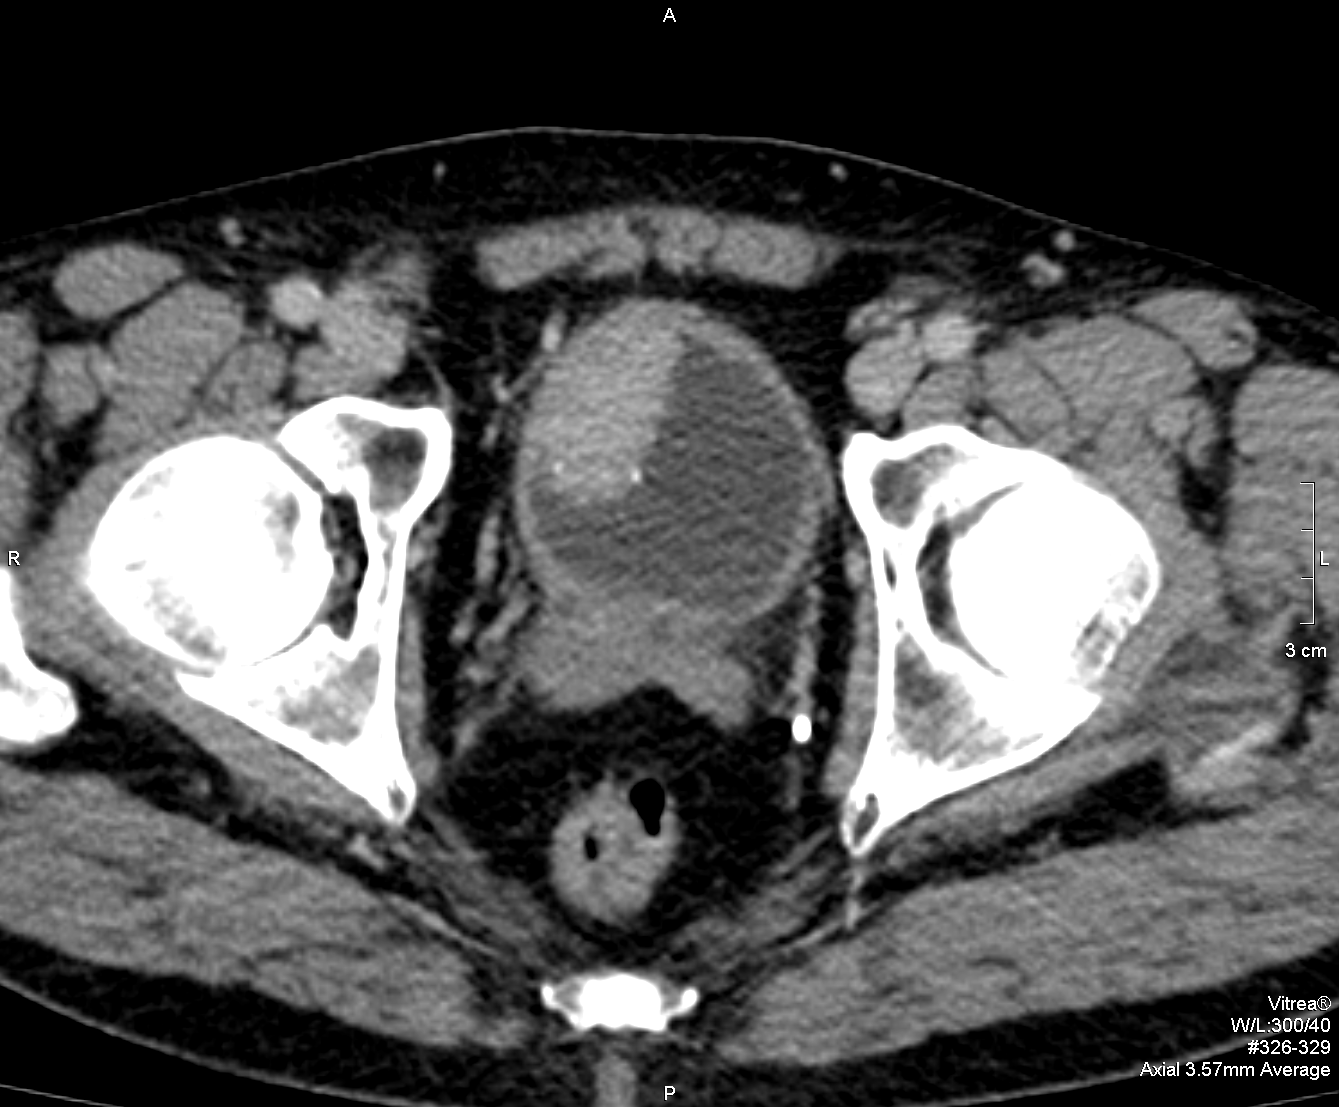

Мочевой пузырь и мочеточники: обструкции, дивертикулы, новообразования

Обструктивные патологии приводят к задержке оттока мочи и могут приводить к изменению формы и размера пузыря, расширению мочеточников или развитию дивертикулов. МРТ позволяет оценить положение дивертикулов, толщину стенок и характер масс в пузыре, что помогает формировать направление к дополнительным исследованиям или лечению.

Оценивается строение почек, чашечек, лоханок, сонных отделов мочеточников и стенок мочевого пузыря. Визуализируются признаки гидронефроза, особенностей оттока мочи и возможных деформаций, что вместе с клиникой помогает определить степень тяжести патологии и выбрать стратегию лечения.

Основные картины включают характерные сигнальные особенности камней, воспалительных изменений и массы в стенке или полости органов. Дифференциация проводится на основе сочетания морфологических признаков на разных линиях и динамики после контрастирования, а также с учётом клинической картины.